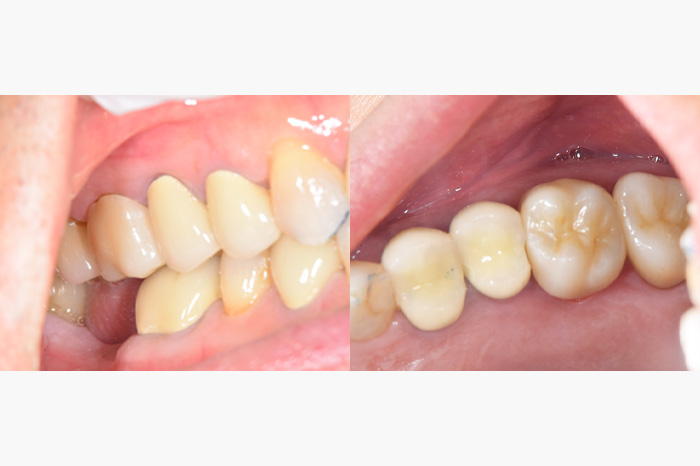

| 年齢 | 40代・男性 |

| 主訴 | 銀歯をなくしたい |

| 治療内容 | 左の銀の詰め物を3本セラミックインレー、右の銀の被せ物を1本ジルコニアステインクラウンにおきかえました。 |

| 治療費 | セラミックインレー: 合計165,000円(税込) (55,000円×3) ジルコニアステインクラウン: 110,000円(税込) |

| 治療期間 | 2ヶ月 |

| リスク・副作用 | 金属を除去すると虫歯になっていることが多いです。そのため、その虫歯を取り除く治療後にしみるといったことがおこります。 症状がおさまらない場合は、神経を取り除くことが必要になることもあります。 |